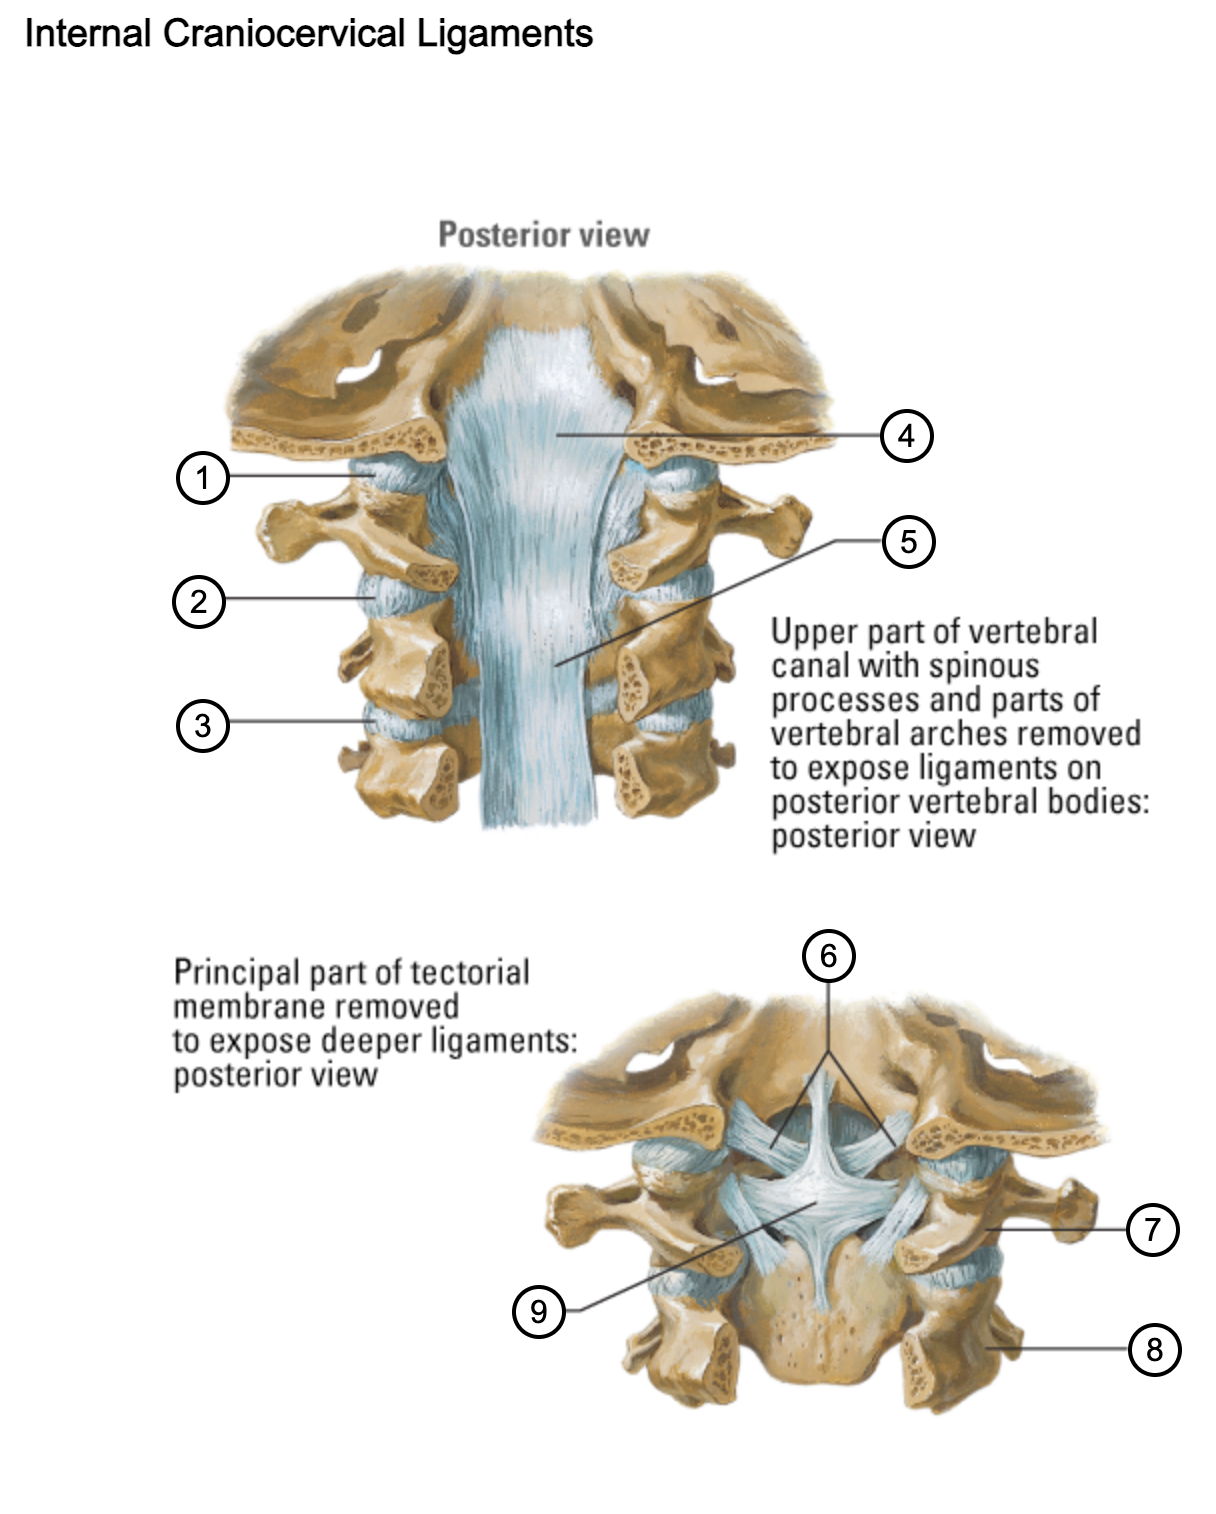

1

capsule of atlantooccipital joint

2

capsule of lateral atlantoaxial joint

3

capsule of zygapophysial joint (between axis and C3 vertebra)

4

tectorial membrane of cervical vertebral column

5

posterior longitudinal ligament

6

alar ligaments

7

atlas (C1)

8

axis (C2)

9

cruciform ligament (superior longitudinal band; transverse ligament of atlas; inferior longitudinal band)